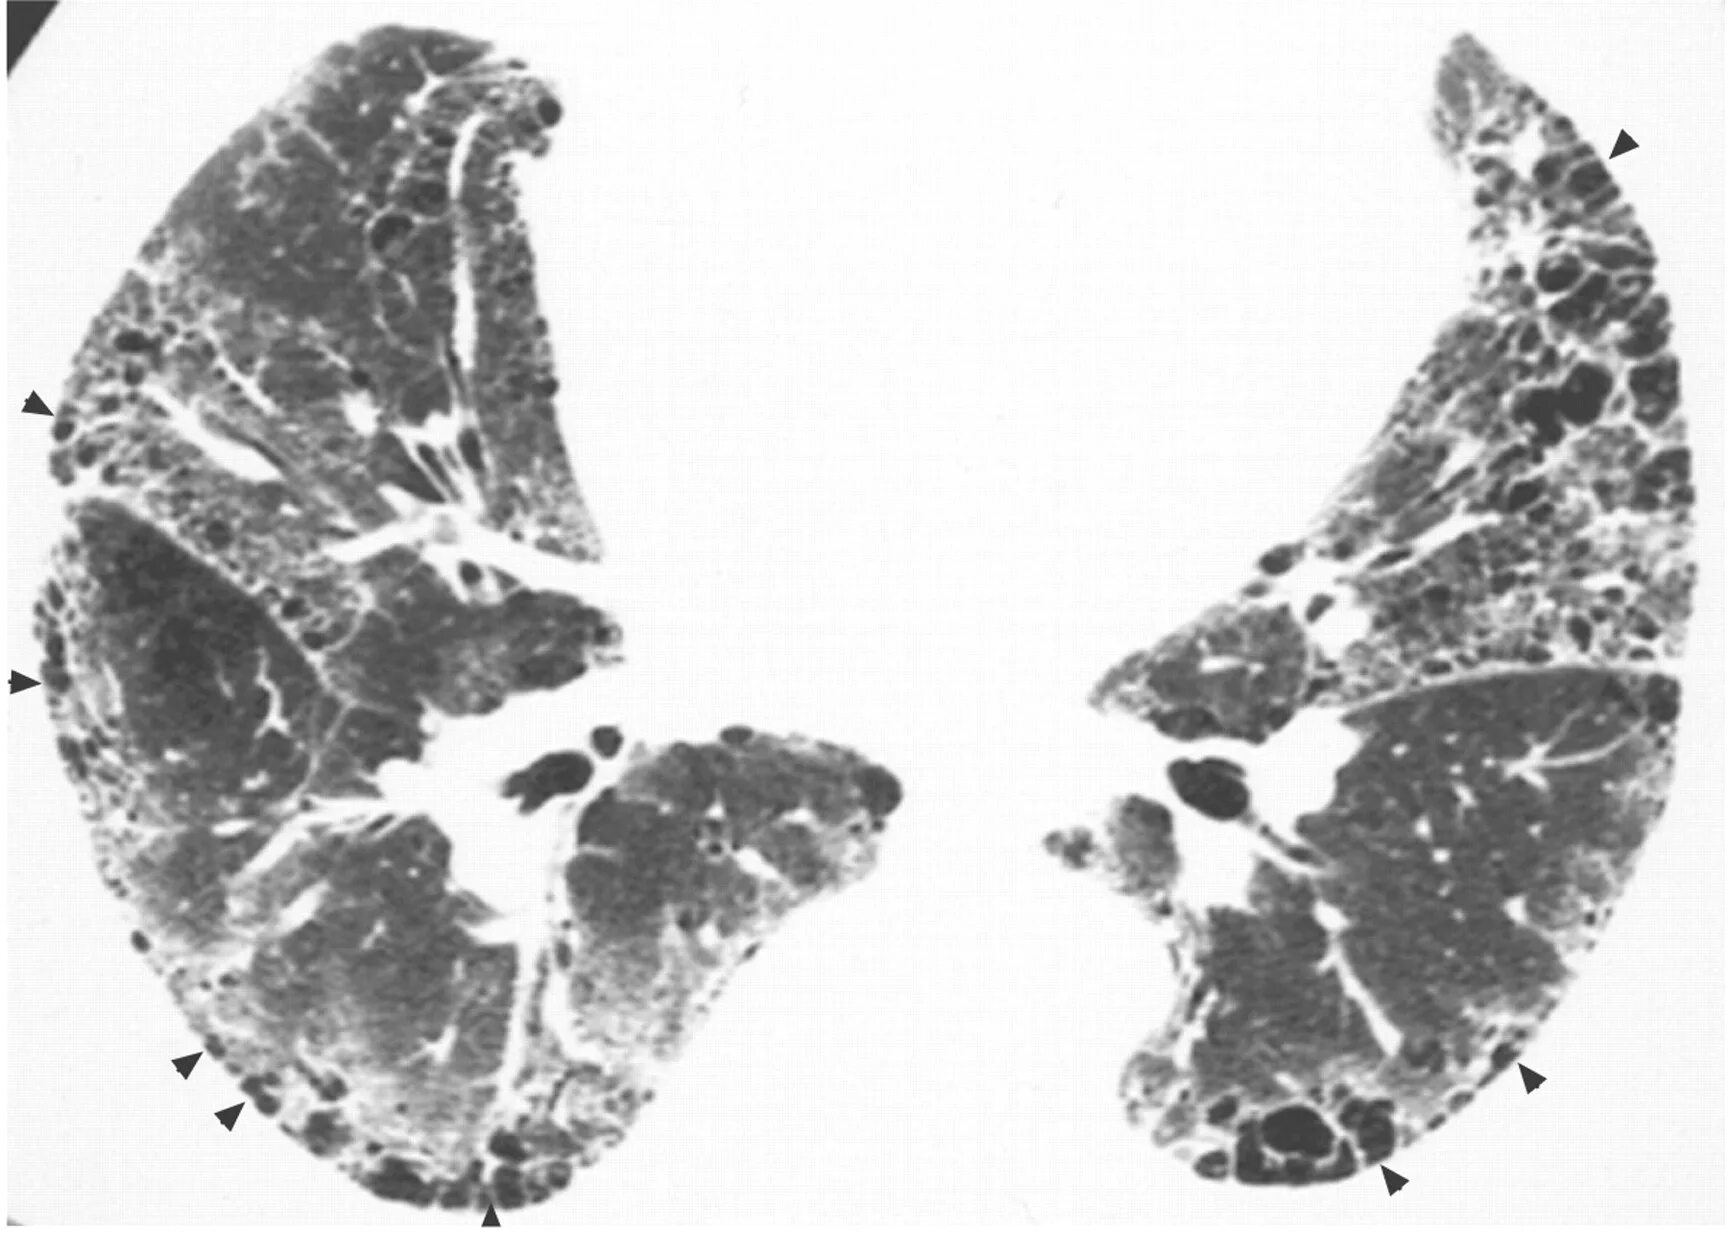

Фиброз кт